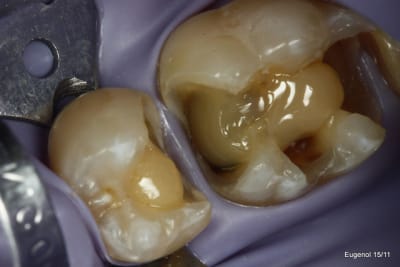

un truc que je fais souvent, quand je monte deux compo volumineux en contact, je monte le plus gros et difficile sans matrice et comme ça j'ai accès a la marge, et je peux donner une jolie forme galbée proximale

puis je monte le suivant avec une seule matrice...

plus facile je trouve d'avoir le point de contact

Attention, je n'ai pas dit qu'il fallait monter les box cuspidés sans matrice....

Je propose cette approche dans les cas particulier où l'on a deux box volumineux face à face. Il est difficile dans ses cas d'obtenir un point de contact efficace.

Je le fais quand je peux facilement avoir accès à la spatule à toute la face proximale